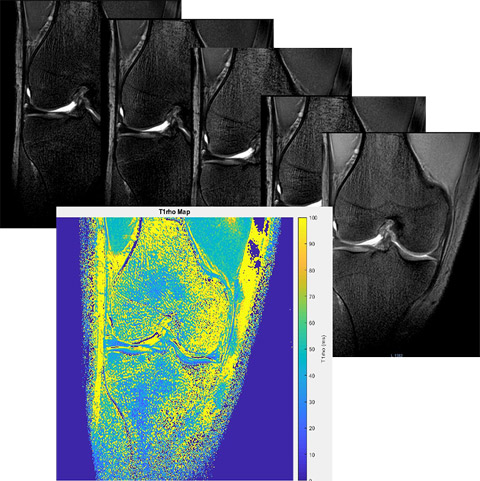

Процесс получения T1rho карт.

Цель Изучить релаксационные показатели Т2, Т1rho-картирования хрящевой ткани суставной поверхности коленного сустава, как количественный критерий выраженности патологий различного характера. Описание проекта Дегенеративные изменения суставов в зависимости от возраста, величины физической нагрузки, в том числе массы пациента, а также сопутствующих заболеваний приводят к изменениям биохимических процессов в хрящевой ткани. Стандартный МРТ протокол позволяет создать достаточный контраст для выявления морфологических изменений в гиалиновом хряще суставной поверхности. На данный момент самым распространенным методом оценки тяжести острых и хронических повреждений суставного хряща из-за своей простоты получили системы классификации, предложенные Outerbridge (1961), Jackson (1988) и Yulish B.S. et al. (1987). Такой подход крайне эффективен в оценке степени хондромоляции, однако не отражает нарушения биохимических изменений в выявленных очагах и зонах поражения гиалинового хряща. Значения релаксационных параметров Т2, Т1rho, получаемых методиками количественной МРТ (qMRI), связаны с физическими свойствами, а также с водным и коллагеновым составом внеклеточного матрикса хряща коленного сустава. Исследование изменения этих параметров при различных заболеваниях, травмах и иных факторах позволит построить точные биофизические модели повреждения хряща, а также потенциально разработать количественные методы определения стадии хондромоляции. Задачи Создание и оптимизация быстрых протоколов сканирования, а также процесса обработки таких изображений для получения Т2 и T1rho карт хрящевой ткани коленного сустава. Получение релаксационных показателей хрящевой ткани суставных поверхностей на примере коленного сустава, в зависимости от степени хондромаляции в разных группах пациентов.

Результаты Разработаны оптимальные протоколы сканирования для получения карт Т2 и Т1rho гиалиновой хрящевой ткани коленного сустава. Проведены измерения значений Т2 хрящевой ткани суставной поверхности коленного сустава у пациентов с рассекающим остеохондритом, а также влияние индекса массы тела на параметры Т2. Результаты представлены на конгрессах: РОРР 2019, Радиология 2018, Радиология 2017